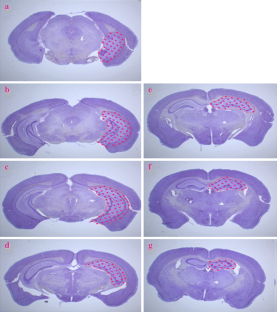

Fig. 2